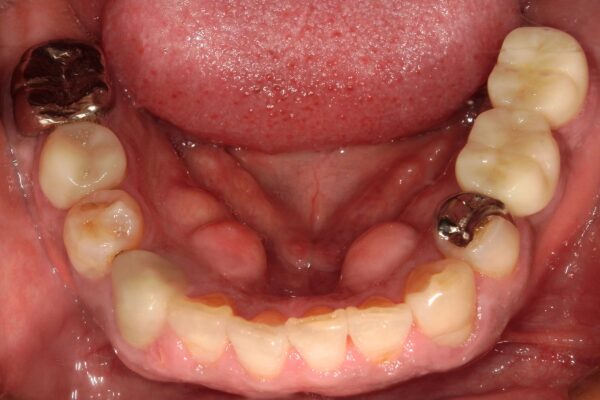

Images